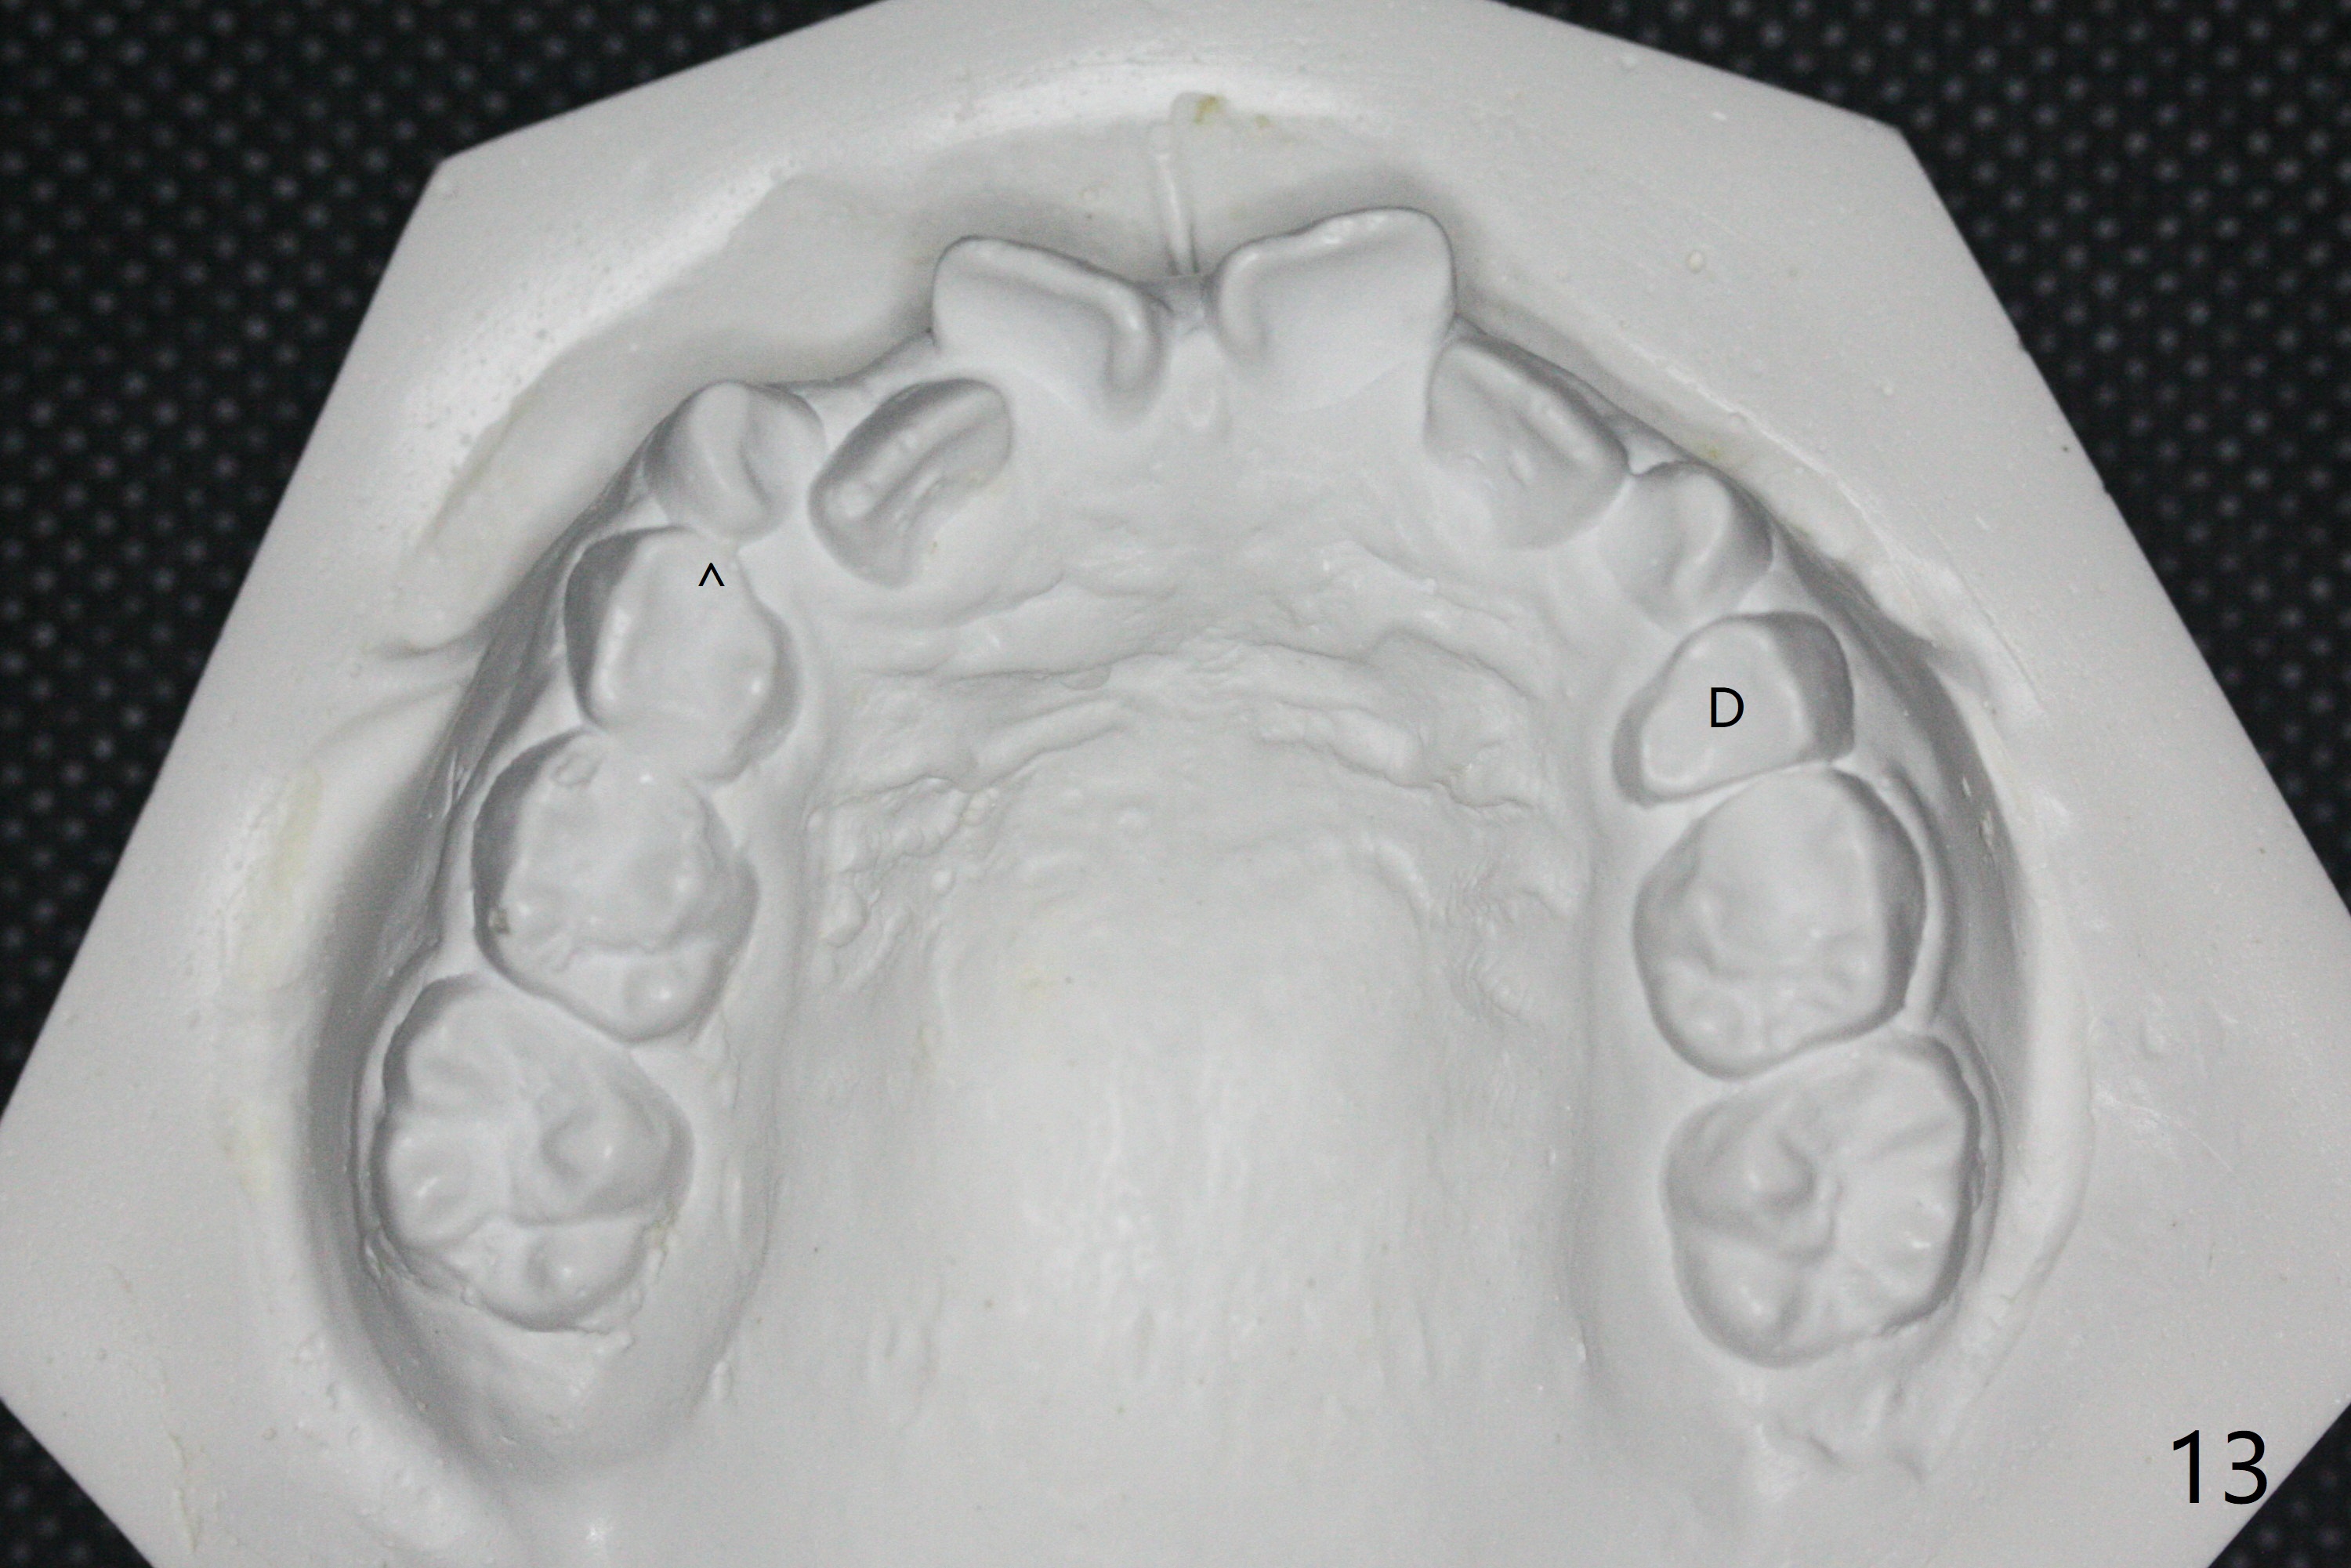

7岁女孩龋齿(图一)到八岁发展的严重(图二,三 (D))。为了有完整支抗,利用树脂(而不是不锈钢牙冠)保留左上第一乳磨牙(图六:D),以后可以安置矫正器。面部匀称(图七至十)。乳尖牙,第一恒磨牙:第一类咬合(图十一,十二)。左上前牙拥挤比右边轻,因为左上D龋齿破坏(图十三:D)。前牙扩弓时,右上D近中需要片切(^)。下颌拥挤轻(图十四),矫正器可以迟放置。